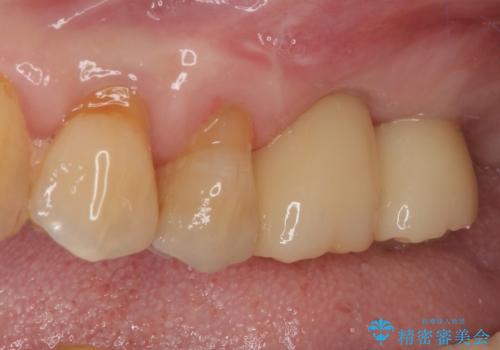

骨量の少ない上顎大臼歯 骨補填材を用いない短期間インプラント治療

- 近医にて入れ歯が合わないためインプラント治療を希望したものの、治療期間が長く大変と聞き、当院を受診された患者様です。

レントゲンから分かるとおり、インプラント埋入に必要な骨の高さが著しく不足している状態でした。

元々の骨量が少なく、通常よりは待機期間が長くなりますが、数ヶ月程度で補綴治療まで行うことができるため、こちらの手法でインプラント補綴治療を行うこととしました。

インプラントが待機期間に脱落することがありますが、一切のトラブルなく、最短期間で無事に治療を終えることができました。